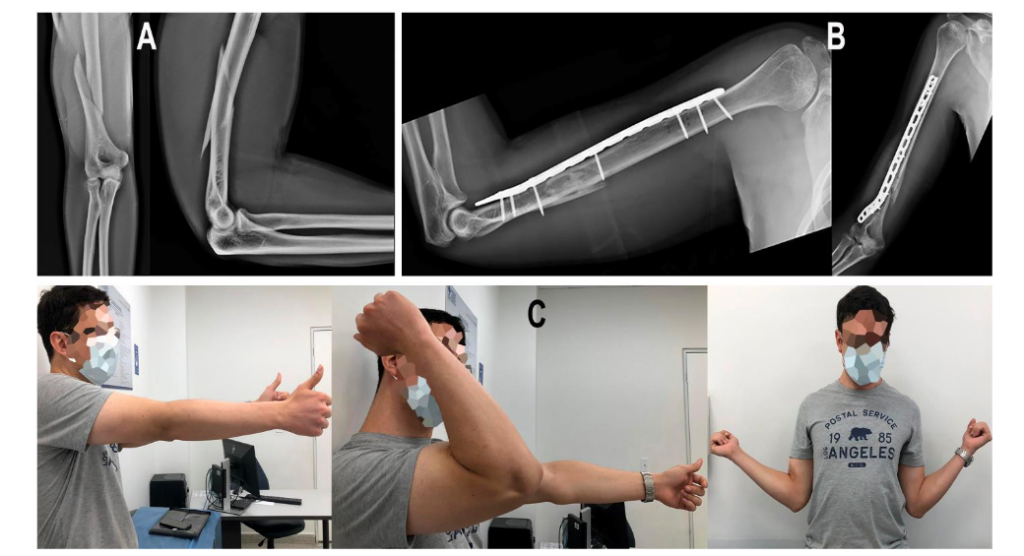

Two cases of the series are shown in Figures 8 and 9.

Figure 9. Case 2.

A. Male, 32 years old, with a right 12-C3 fracture.

B. Three months’ follow-up.

C. AROM at three months after surgery.